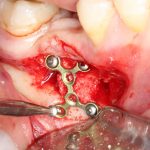

Я зафиксировал костный блок практически без адаптации на несколько винтов. Обрати внимание, что винты находятся в зоне, где не планируется установка имплантатов. Фиксация должна быть надежной, поскольку мне еще предстояла подготовка лунок для имплантатов. Трех винтов для этого вполне достаточно.

Дальнейшая адаптация костного блока свелась к сглаживанию острых краев. После чего я приступил к подготовке лунок и установке имплантатов.

Напомню, что для этой работы я выбрал субкрестальные имплантаты Ankylos C/X. Они прекрасно сочетаются с любым методом остеопластики.

Я не планирую установку супраструктур или коронок, поэтому на уровень первичной стабильности можно положить болт. Даже наоборот — чем меньше крутящий момент при установке, тем лучше. Для имплантатов Ankylos и подобных им, это особенно важно. В общем, момент силы при установке — не более 10-15 Нсм.

Ремарка: имплантаты с предустановленными имплантодержателями хороши тем, что с ними легко контролировать позиционирование имплантатов. В случае с Ankylos С/Х - еще и крутящий момент. Имплантодержатель должен отсоединяться от имплантата с легким щелчком. Если его клинит, и тебе приходится прикладывать для этого усилия, то ты, однозначно, превысил момент силы во время установки имплантата. Следовательно, жди проблем.

Глянем на то, что получилось: